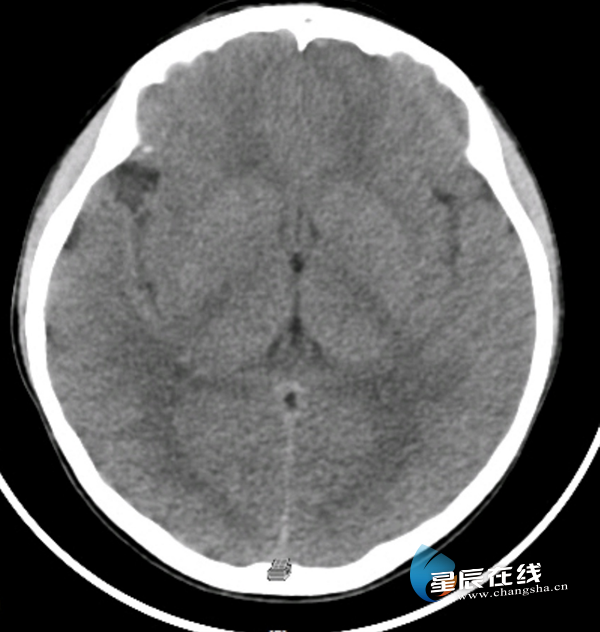

CT可以理解为“立体X光”,它通过环绕扫描,获取人体一层一层的断面图像,再重组成三维影像。它能看清更细微的结构,比如肺部小结节、脑出血等,是发现早期肿瘤、评估复杂伤情的重要工具。

(头部CT影像示例,显示脑部结构。)